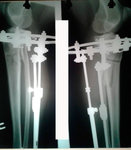

Отправляю вам контрольные рентген-снимки и фото ножек. Со дня снятия прошло 50 дней.

Здравствуйте, Наталья! По рентгену, всё отлично! разрешено всё без ограничений! Исключить: беременность в течении первых 6 месяцев.